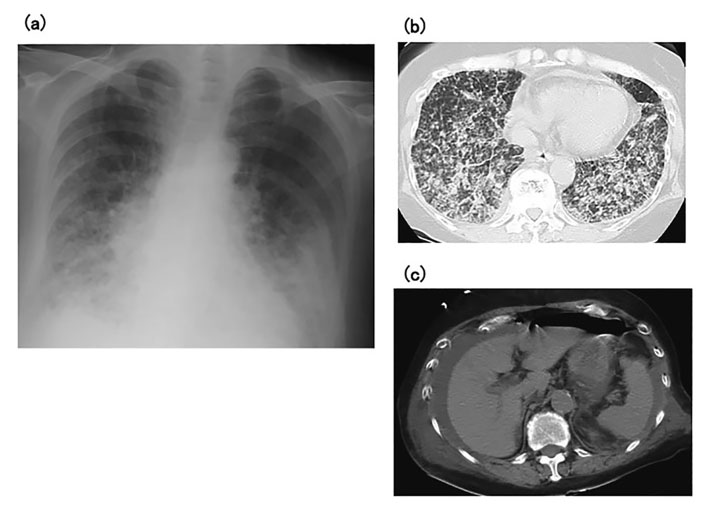

A 66-year-old woman was admitted to our hospital with severe dyspnea. She had developed arthritis of her bilateral wrist joints 7 years earlier, and had been diagnosed with RA. She was initially administered bucillamine with no improvement in her wrist pain, but her joint pain was relieved after the addition of MTX 6 mg/week. Pain in her bilateral knee joints worsened 5 years after her initial diagnosis but was controlled by increasing the MTX dose to 12 mg/week. On admission, her axillary temperature was 37.2°C, blood pressure was 125/69 mmHg, and oxygen saturation was 90% under oxygen inhalation at 10 L/min. There were no palpable swollen lymph nodes on physical examination, and no evident skin ulcers or rashes. Fine crepitations were audible by chest auscultation over both lungs. No swollen or tender joints were identified in the upper or lower extremities. Laboratory findings were as follows: white blood cell count, 22,700/μL (neutrophils, 72%; monocytes, 4.5%; lymphocytes, 8.5%; atypical lymphocytes, 2.5%); hemoglobin, 12.8 g/dL; platelet count, 81,000/μL; total protein, 4.9 g/dL; albumin, 2.8 g/dL; lactate dehydrogenase, 545 U/L; C-reactive protein, 6.11 mg/dL; β-D-glucan, < 6.0 pg/mL; and soluble interleukin-2 receptor, 11,000 U/mL. Chest X-ray and computed tomography (CT) of the neck, chest, and abdomen showed severe and extensive interstitial shadows in bilateral lung fields, but no lymphadenopathy (Fig. 1a, b). Acute exacerbation of interstitial pneumonia was diagnosed, with MTX-induced interstitial pneumonia, Pneumocystis jirovecii pneumonia, or RA-related lung complications as possible causes. MTX administration was therefore suspended on hospital day 1, and the patient was treated with methylprednisolone pulse therapy at 500 mg/day and trimethoprim-sulfamethoxazole combination at 9 g/day for 3 days. Respiratory management was initiated using noninvasive positive-pressure ventilation due to low oxygen saturation. However, the patient’s respiratory condition failed to improve, despite these measures. On hospital day 4, the patient complained of worsening abdominal pain after eating some jelly. A chest X-ray the following day showed free air under the right diaphragm, and CT showed massive abdominal effusion and free air in the abdominal cavity (Fig. 1c). Perforation of the digestive tract and peritonitis were diagnosed and immediate abdominal surgery was performed. The perforation site was identified as the terminal ileum (about 30 cm oral to the ileocecal region) (Fig. 2a), and the patient underwent partial excision around the perforated region and intraperitoneal cleaning drainage.

(a) Chest X-ray on admission shows reticular shadows in both lungs. (b) Chest computed tomography on admission shows extensive interstitial shadows in both lungs, particularly in the lower lung fields. (c) Chest computed tomography on hospital day 4 shows a water-density mass around the liver and free gas in the abdominal cavity.